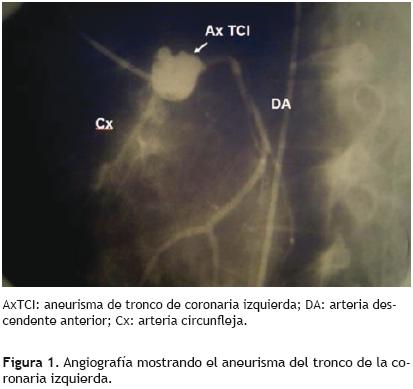

La paciente reingresó el 06/02/1996 para coronariografía de control, que reportó ACx permeable y aneurisma del tronco de la coronaria izquierda (Figura 1). En la resonancia magnética se observó una imagen sugerente de trombo (Figura 2). Por el gran tamaño del defecto vascular se consideró manejo quirúrgico del aneurisma, sin embargo se determinó de alto riesgo quirúrgico dadas las comorbilidades de la paciente (SAF, eventos previos de trombosis: TEP y TVP), y ante el hecho que se encontraba asintomática, se decidió continuar tratamiento conservador con base a anticoagulación oral y antiplaquetario.